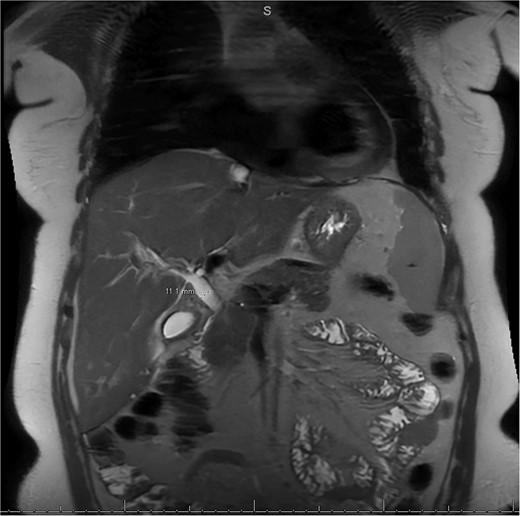

A 49-year-old female with a history of ADPKD and multiple liver cysts, 13-months status post subtotal cholecystectomy, endoscopic retrograde cholangiopancreatography with biliary sphincterotomy and balloon stone extraction, presented to the emergency department with fever and a 4-day history of discomfort in the right upper quadrant. At the time of the initial cholecystectomy, total cholecystectomy could not be performed due to extensive adhesions, and subtotal cholecystectomy with complete evacuation of the stones was done instead. Magnetic resonance cholangiopancreatography (MRCP) done at that time showed a dilated common bile duct (CBD) to 1.5 cm, intra and extrahepatic biliary dilatation, multiple liver cysts measuring up to 2 cm, and multiple stones in the CBD, including at the level of the ampulla (Fig. 1). Computerized tomography scan at the time of the second admission showed acute cholecystitis and she had mildly elevated transaminases, but there was no evidence of cholestasis or pancreatitis. MRCP showed minor proximal intrahepatic biliary dilation and cholelithiasis but no duct calculi (Figs 2–4). A laparoscopic cholecystectomy was attempted with extensive adhesiolysis between the gallbladder and surrounding omentum and mesocolon, but the cystic duct could not be isolated, and ultimately the cased was converted to open. While removing the gallbladder in a top-down fashion, a small bile leak was identified right at the closed end of the gallbladder remnant, where the bile duct was adhered to the gallbladder wall. Intraoperative cholangiogram was obtained through a small perforation in a right posterior bile duct at the site of attachment, which showed right posterior, right anterior and left hepatic ducts of equal size converged at a trifurcation (Fig. 5). The duct was repaired over a T-tube and observed throughout the rest of the case and no bile leak was identified. The gallbladder was opened along its lateral edge, revealing a hugely dilated cystic duct with ~10 to 12 marble-sized stones packed within the gallbladder remnant and cystic duct down to the juncture with the common bile duct. All the stones were removed and the safe portion of the gallbladder remnant was resected leaving the side attached to the bile duct in situ due to the Mirizzi anatomical variant. The cystic duct was oversewn along with the remnant of the gallbladder wall. Pathology showed acute-on-chronic cholecystitis with cholelithiasis. Repeat MRCP showed no retained stones in the biliary tree. The recovery course was unremarkable.

MRI/MRCP from second hospitalization demonstrating CBD of 1.1 cm.